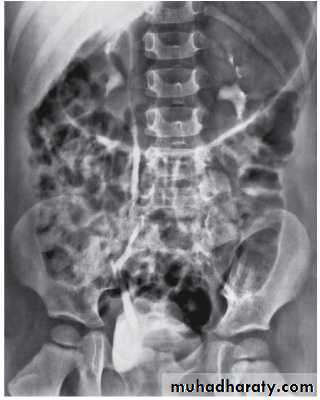

Grading of VUR

The degree of reflux is graded I–V.Grading is based on the appearance of contrast agent in the collecting system during voiding cystourethrography (VCUG(.